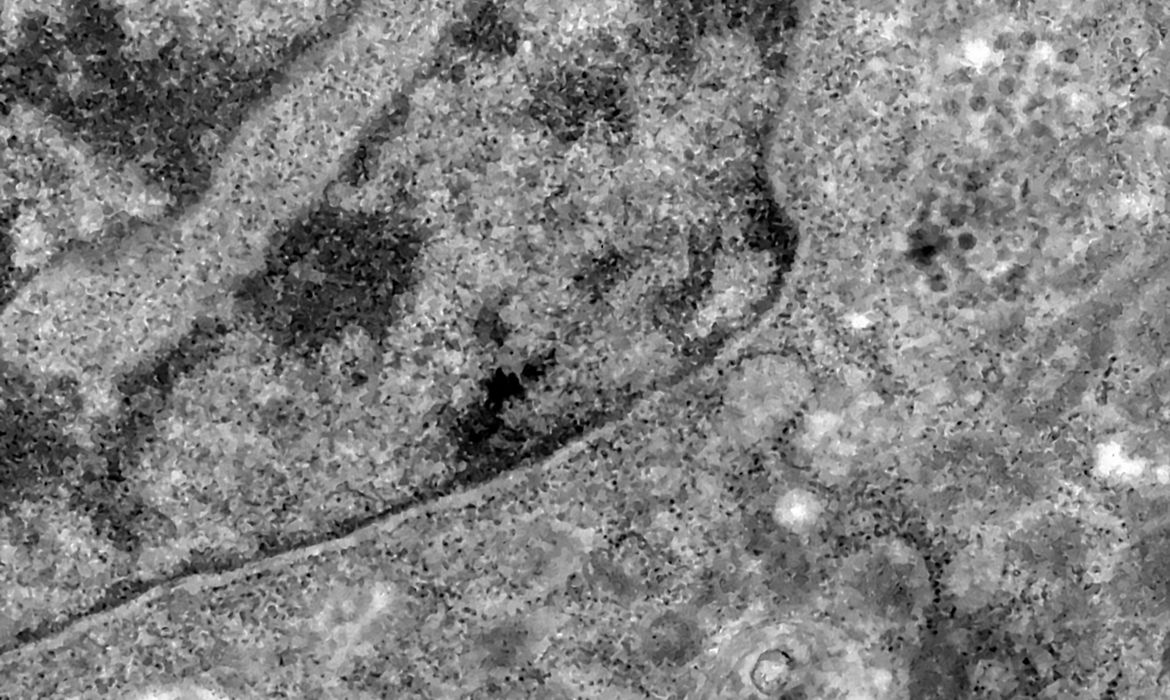

Os pesquisadores analisaram retinas de pacientes que morreram em decorrência da covid-19 e compararam com fotos dos olhos desses pacientes quando vivos para analisar as diferenças e formas de aferir a presença do vírus a partir da retina.